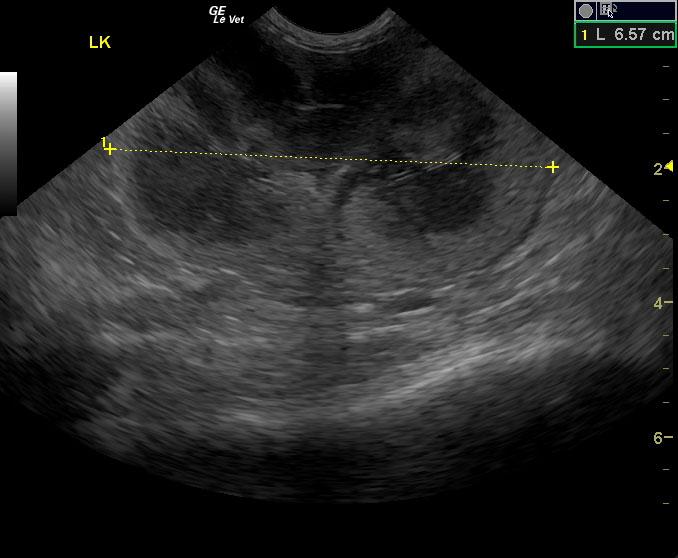

A seven-year-old MN DSH cat was presented with lethargy with the owner reporting that the cat’s behavior and temperament had changed. On urinalysis the urine was straw in color and clear; USPG was inappropriate (1.021), hematuria was present. The urine protein/creatinine ratio was 1.1. Abnormalities on CBC and serum chemistry were anemia, neutrophilia, lymphopenia, monocytosis, hypoproteinemia, and azotemia. Abdominal radiographs revealed an left nephromegaly and a mass effect in the gastrointestinal tract.